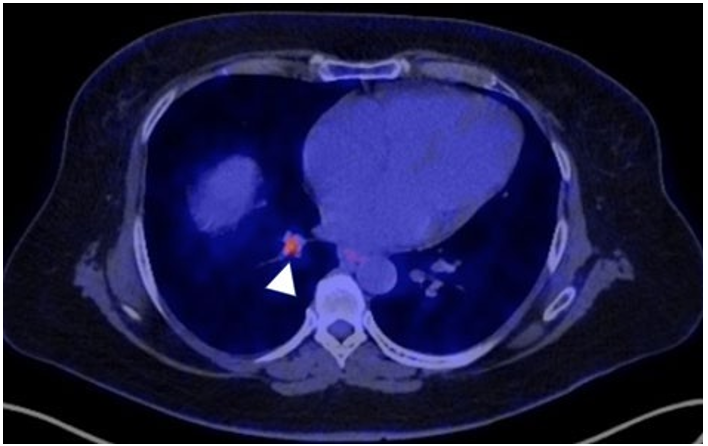

One of 13mm with central position, and others of 9- and 6-mm peripherals, without mediastinal adenopathy’s. PET-CT hypermeta- bolic lesion with SUV: 3.88 corresponding to the 13mm nodule (figure 2).

Figure 2: PET-CT: 13mm Pulmonary Nodule with SUV 3.88 (white arrowhead)